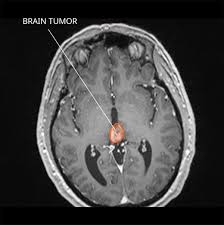

The diagnosis of pineal cyst is usually established by MRI with defined radiological criteria to distinguish benign pineal cyst from tumors of this area. A pineal cyst is usually only treated if it causes symptoms. In order to detect the presence of a cystic mass in the head magnetic resonance imaging is required.

Surgical removal is the most common treatment for pineal cyst. Pineal cysts tend to be more common in. The diagnosis of pineal cyst is usually established by MRI with defined radiological criteria to distinguish benign pineal cyst from tumors of this area. Surgical interventions have been used to remove the cyst and resolve symptoms37 These approaches include both. Some tumors are sensitive on radiationOutcome of the surgery depends on size and type of tumor. A neuro-ophthalmologist can be very helpful in defining vision and eye movement problems and can determine if these problems are related to the cyst. If symptoms are present your healthcare provider may recommend these treatments. Since your headaches might not be due to the pineal gland cyst discuss with your doctor other possible causes for your headaches. Pineal Cysts are fluid structures that form on the pineal gland and are treated when they are large greater than 2cm and cause symptoms such as debilitating headaches or eye movement problems.